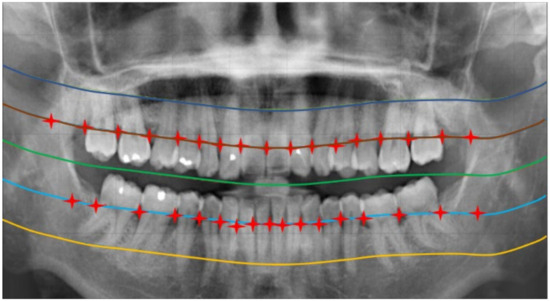

2.2.1. Curve of the Mouth

2.2.2. Curve Adjustment